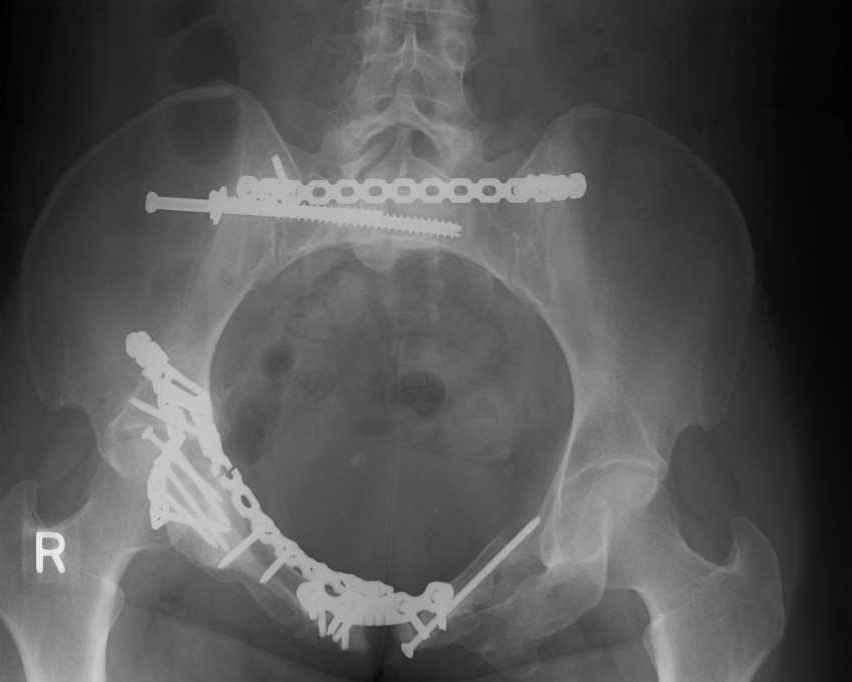

Looking for advice. This is a 48 yo non-smoking female s/p MCC 10 months ago. I do not have the initial injury films. She underwent ORIF as shown on attached file. She is having continued pain in low back/sacral region. Worse with sitting and prolonged walking. Has had pain since surgery. All of her wounds have healed uneventfully. Also has right hip pain laterally. No groin pain. Not aggravated with ROM of the hip. Infection work-up has been negative.

Any thoughts on the broken plate on the pelvic brim and the non-union on the anterior column. Doesn't seem like she's have pain from there.

Suggestions on treatment of sacral nonunion.